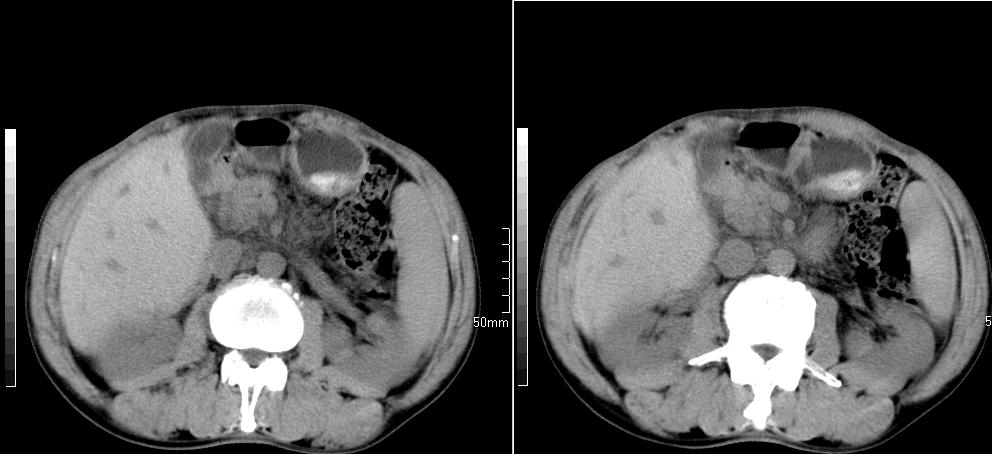

标题: CT26769:男,58岁,腹胀、腹部不适一年余 [打印本页]

标题: CT26769:男,58岁,腹胀、腹部不适一年余

肠系膜脂膜炎,胆囊炎,脾大。建议结合临床。鉴别:慢性胰腺炎并假囊肿形成。

1 慢性胰腺炎并假囊肿形成。2 慢性胆囊炎并累及肝边缘!

1)考虑慢性胰腺炎并假性囊肿形成。2) 慢性胆囊炎。3)肝内胆管扩张。

1肝内胆管扩张,性质待定,2慢性胰腺炎胰管扩张,胰腺颈部假囊肿,3肝左叶低密度为小囊肿,4胆囊炎。

1)考虑慢性胰腺炎并假性囊肿形成。2)肝内胆管稍扩张。